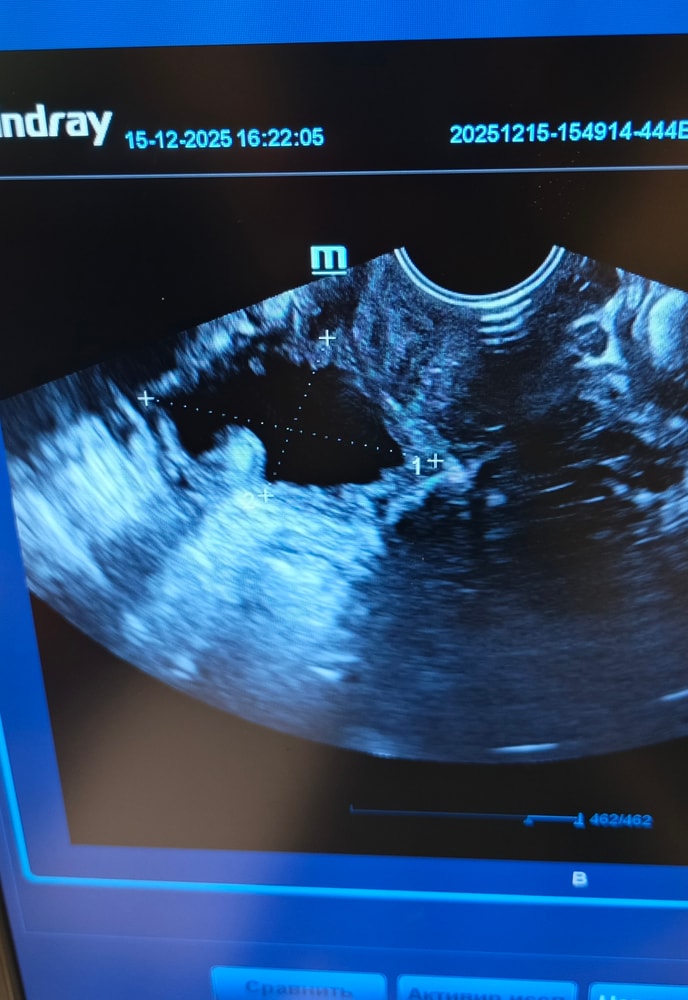

Все я устала ничего не хочу уже. 😔 Была опять сегодня на узи 🤦 Овуля поздняя была , жт какое то странное . Кистозное. Больше похоже на перерождение в кисту . Стенки как у медузы. Еще и сосечек какой то внутри хз страх да и только. По фоликам вообще молчу там даже смотреть нечего. Больше всего расстроил кровоток в эндометрии его как бы нет. ⛔ 🗿🥺 Эндик если до этого был 10мм в нижней трети в дне 6мм. То сейчас в дне 8,9-10 в нижней трети 6. Не знаю, я что делать. Препараты для кровотока пью. Физио прошла. От хэ пролечилась 💊. Эстрогены были прог ставила. Походу так до переноса я не дойду 🙄🥺.

Посмотрите снимки может есть какие мысли ?? 🤔 🙏